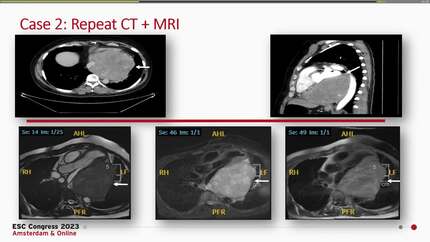

Myocardial infiltration by a primary mediastinal large B-cell lymphoma: A case report